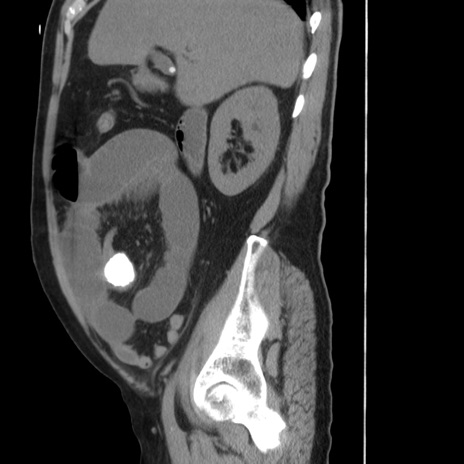

症例20(矢状断像)

【症例】 60歳代男性

【主訴】 腹部膨満、嘔吐

【現病歴】5日前頃より倦怠感を認め食事量減少し4日前の朝嘔吐、食事摂取困難となった。 3日前近医受診し点滴施行され整腸剤などを処方された。 当日他院を受診し、腹部膨満著明、炎症反応の上昇(CRP10.8、WBC11200)あり、紹介受診となる。

【身体所見】 意識JCS1 受け答えがはっきりしないBP 111/57mHg、 P 67bpm、、BT35.2°C、SpO2 97%(RA)、 腹部:膨隆、打診で鼓音あり、全体的に圧痛有り、腸蠕動音(-)、反跳痛ははっきりせず。

【データ】WBC 11400、CRP 14.20